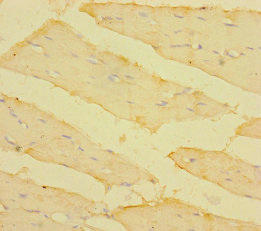

Immunohistochemistry of paraffin-embedded human skeletal muscle tissue using CSB-PA023620LA01HU at dilution of 1:100